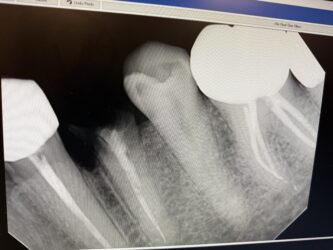

Looking for some feedback and advices. #21 was extracted and placed immidate 4.1×12. I know I needed to go 2-3 mm beyond the apex, however, I didn’t have the correct length. The final torque was about 20 NCM. Bone graft was added and collagen plug and sutured with chromic gut. Please evaluate the radiographs and advise. When should I schedule for follow up?

Everything looks fairly solid on the xray to me. I would follow up 4 weeks post op and see how things are progressing.